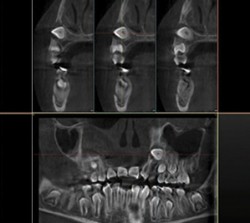

3D Cone Beam Imaging

3D volumes produced with “I-Max Owandy 3D” are used to assess bone quality to implant area and to view all the surrounding anatomic structures

through different planes.100€60€ -

3D Cone Beam Imaging

3D volumes produced with “I-Max Owandy 3D” are used to assess bone quality to implant area and to view all the surrounding anatomic structures

through different planes.100€60€ -